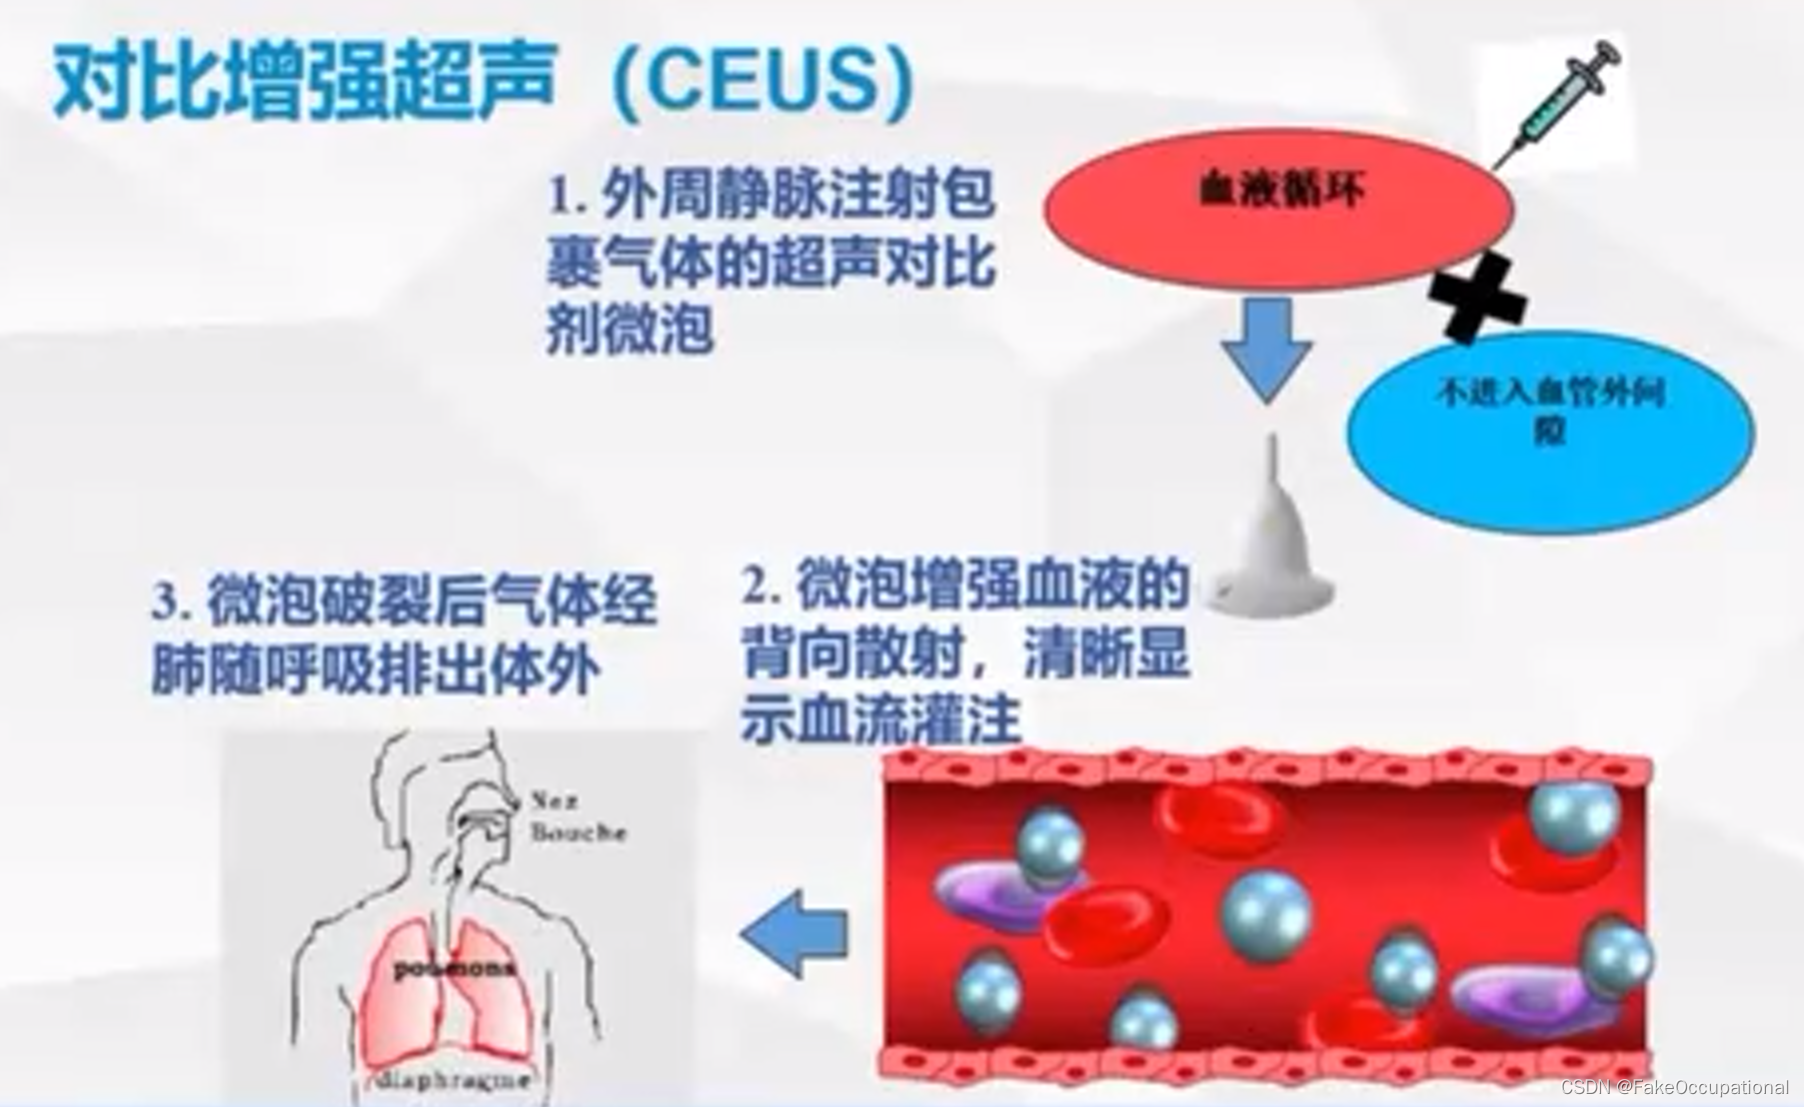

超声新技术

1.三维超声

2.超声造影

3.弹性成像

- 超声更多起一个筛查的作用,定性需要造影或者其他设备的辅助

- 超声造影